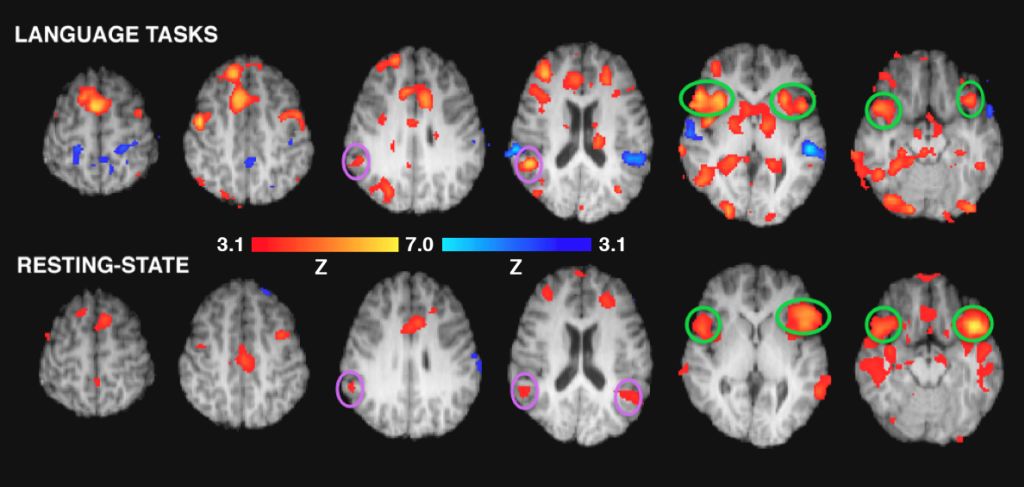

“Am intrat în acest studiu având în minte ideea de a vedea modul în care rețelele creierului sunt influențate de poveste”, explică Hutton. Una din zonele observate a fost cea a limbajului. O alta a fost cea a percepției vizuale. Cea de a treia este numită zona imaginației vizuale. Iar cea de a patra este rețeaua default mode (funcționare implicită), pe care Hutton o denumește “sediul sufletului și al reflecției interne – care arată în ce măsură ceva contează pentru tine.”

În condițiile audiției audio simple (care este ”prea rece”) au fost activate rețelele limbajului, dar conectivitatea generală cu celelalte zone a fost mai slabă. “Existau mai multe dovezi că copilul se forța să înțeleagă.”

În condițiile urmăririi desenului animat (care este ”prea fierbinte”) s-a observat multă activitate în zonele și rețelele percepției audio și vizuale, dar nu foarte multe conexiuni cu variatele rețele ale creierului. ”Rețeaua limbajului lucra intens pentru a ține pasul cu povestea,” spune Hutton. “Interpretarea noastră a fost că filmul animat face munca în locul copilului. Copiii cheltuiau majoritatea energiei doar pentru a-și da seama ce înseamnă ceea ce văd/aud.” În această situație, înțelegerea poveștii a fost cea mai slabă.

În condițiile vizualizării ilustrațiilor dintr-o carte în timp ce urmăresc audio povestea, s-a dovedit că această combinație este cea potrivită.

Atunci când copiii au putut vedea ilustrațiile, intensitatea activității rețelei neuronale a limbajului a scăzut puțin în comparație cu activitatea din zona percepției audio. În loc să acorde atenție doar cuvintelor, spune Hutton, înțelegerea de către copii a poveștii a fost structurată de indiciile oferite de imagini.

Cel mai important, în situația unei cărți ilustrate, cercetătorii au văzut o conectivitate crescută între și în interiorul tuturor rețelelor neuronale la care s-au uitat: percepția vizuală, imaginația vizuală, limbajul și acea default mode (reflecția internă).